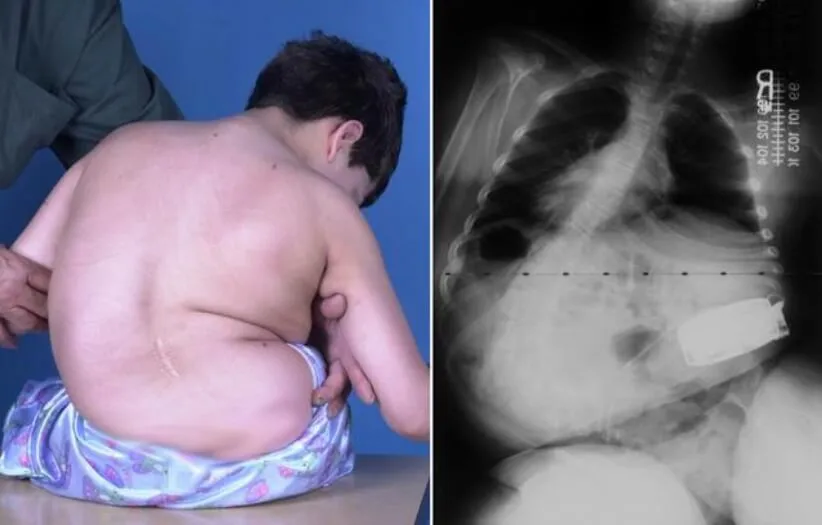

The process of diagnosing neuromuscular scoliosis in children typically initiates with a thorough physical examination conducted by a healthcare professional.

During this examination, the child’s doctor routinely gathers the family’s medical and genetic history, inquires about the onset and nature of symptoms, and conducts a comprehensive assessment of the child’s spine and back. The examination includes evaluating issues related to balance, movement, skin integrity, and the presence of functional deficits.

For instance, in the case of an adolescent with cerebral palsy who is confined to a wheelchair and exhibits a significant left-bending scoliotic curve, this may lead to a pelvic tilt, contributing to sitting imbalance and the potential development of sitting sores.

X-ray imaging plays a crucial role in the assessment and diagnosis of neuromuscular scoliosis. The Cobb angle, measured during X-rays, serves as the orthopedic gold standard for evaluating scoliosis severity and is categorized on a scale:

- Mild scoliosis: Cobb angle measurement between 10 and 25 degrees

- Moderate scoliosis: Cobb angle measurement between 25 and 40 degrees

- Severe scoliosis: Cobb angle measurement of 40 degrees or more

- Very-severe scoliosis: Cobb angle measurement of 80 degrees or more